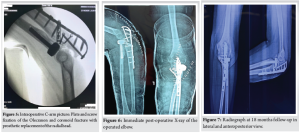

The goal of surgery was to achieve anatomical reduction and fixation of fractures, replacement of radial head, and repair of injured ligaments, if any, thereby achieving enough stability of the elbow for allowing early mobilization. We had 2.5 mm and 3.5 mm plating sets, radial head prosthesis, and suture anchors in our armamentarium before going in for surgery. The next issue in our planning was exposure since we had to address all three components of the TTE along with the olecranon. The radial head and lateral ulnar collateral ligament injury (if found to be present) would have required a lateral Kocher or Kaplan approach. Now, we would have been left with fixing olecranon and coronoid. Usually, for olecranon, the approach is pure posterior and for coronoid (and for addressing possible MCL injury), it is pure medial. Hence, to address both the fractures-olecranon and coronoid, the planned incision was midway, that is, posteromedial. The patient was operated in a lateral decubitus position with the arm supported over an arm holder. The surgery was done under a tourniquet. Kocher’s lateral approach was used to reach the radial head. It was found to be comminuted with multiple small irreparable fragments. The fragmented radial head was removed and a radial head arthroplasty (Fig. 3) was done. Next, a posteromedial incision was made, somewhere between the medial FCU split approach and the posterior approach between FCU and ECU for fixing olecranon. The skin and subcutaneous tissues were raised as a single flap to preserve the vascularity. On deeper dissection, we digressed on either side of the ulnar head of FCU. On the lateral side, the plane between FCU and ECU was used for fixing the olecranon. On the medial side of the ulnar head of the FCU, the ulnar nerve was isolated from between the two heads of the FCU. This FCU split approach was used to reach coronoid. The ulnar head of FCU had to be adequately mobilized for achieving this (Fig. 4). Olecranon plating was done using a 3.5 mm pre-contoured anatomical plate. The coronoid process, which is the key to elbow stability, was fixed through 2 large screws from posterior to anterior and buttressed by a 2.7 mm T-plate (Fig. 5). At this stage, AP and mediolateral stability of the elbow was assessed by fluoroscopy in the functional range of motion (ROM) of 30° to 130°. The elbow was found to be stable with no incongruency. Post-operatively, an above elbow slab was applied in 90° flexion and pronation for 3 weeks, following which active ROM exercises were started along with radiographic check X-rays at each visit to check for joint congruency and stability (Fig. 6).

At the final follow-up at 18 months (Fig. 7), the patient was mostly pain-free and able to perform his normal routine activities. His elbow was stable, and the ROM in the flexion-extension arc was 10°–130°. The supination and pronation reached 80° each way (Fig. 8). The Carrying angle was around 10° of valgus in maximal supination. There was no evidence of heterotrophic ossification of the elbow leading to a limitation of movement. Based on these findings, the mayo elbow performance index (MEPI) [11] was calculated, and the functional outcome was found to be excellent.